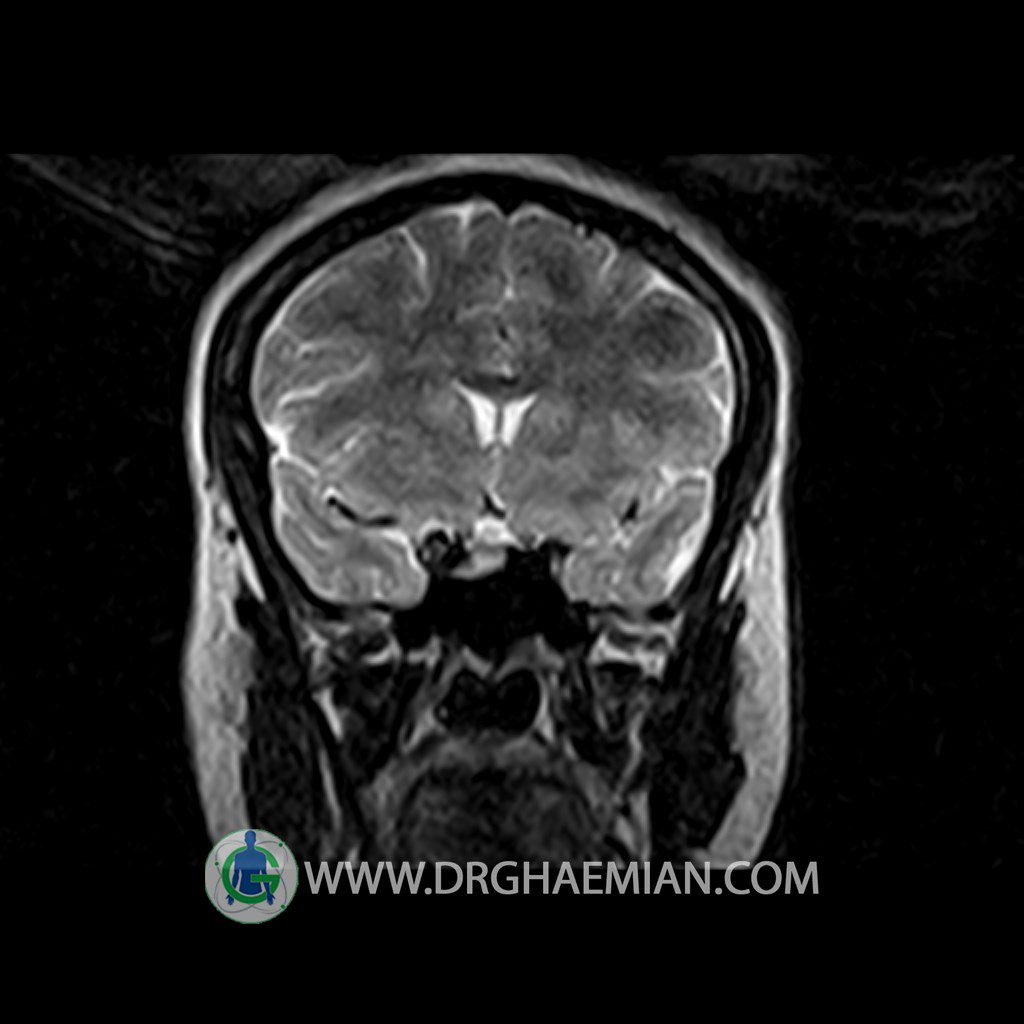

ام آر آی هیپوفیز یک روش تصویر برداری است که از غده هیپوفیز (غده ایی کوچک در مغز که هرومون ها و دیگر غدد بدن را کنترل می کند) و ناحیه های پیرامونش در مغز تصاویری ایجاد می کند. در این کیس سلای نسبتا خالی در ناحیه هیپوفیز بیمار مشاهده می شود.

The pituitary tissue shows normal , position, shape , size and homogeneous signal intensity both before and after contrast administration .

Anterior and posterior pituitary gland were normal .

The infundibulum is centered and of normal size .

The optic chiasm and suprasellar spaces appear normal .

– Extension of suprasella cistern to sella with thin pituitary gland in floor of sella ( partial empty sella )

is seen